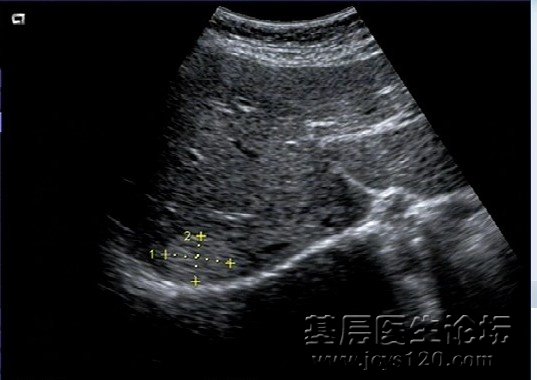

• 肺结核还是肿瘤? attach_img agree

• sxmz 2012-6-11

• 2、女性,65岁,哮喘、肺气肿病史十余年,因发热、咳嗽、咳痰一周入院,昨天在医院检查WBC22.3×10 9 白蛋白低于正常值,总胆红素稍高(具体数值稍后补上) 肝脏超声检查:肝硬化并内见多个低回声结节,少量腹水。 ...  阅读全文>